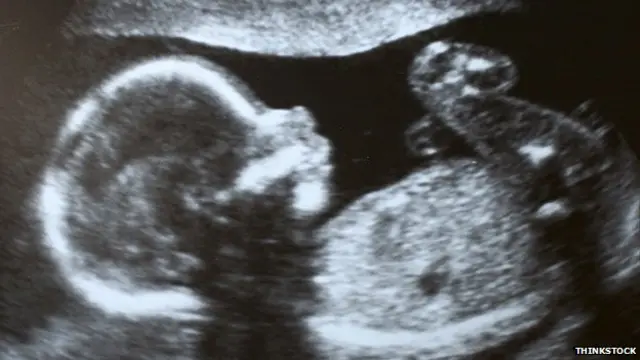

सुप्रीम कोर्ट ने एक रेप पीड़ित के गर्भ में पल रहे 24 हफ्ते के 'असामान्य भ्रूण' को गिराने की इजाज़त दे दी है.

सुप्रीम कोर्ट ने कहा कि मेडिकल बोर्ड ने करीब 24 महीने के भ्रूण में गंभीर असमान्यताएं पाई हैं.